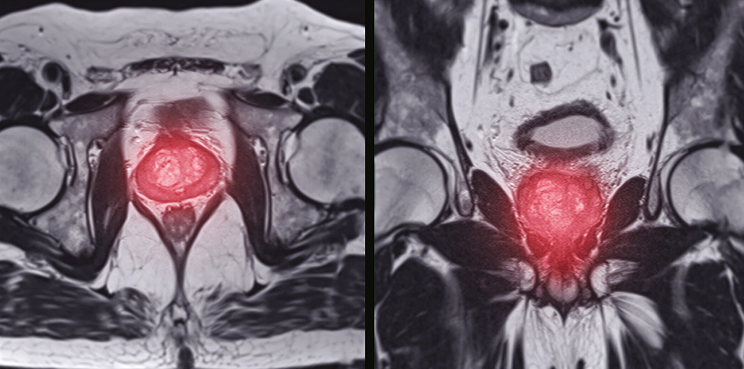

Complex MRI images contain vast information, but without expert labeling and segmentation, even the most advanced algorithms cannot learn effectively. Pareidolia Systems LLP, our annotation specialists combine medical expertise and advanced tools to deliver pixel-level accuracy in marking cancerous and non-cancerous regions. These annotations enable AI models to:

Segmentation and 3D Modeling: A New Dimension to Cancer Analysis

Traditional 2D medical imaging has its limits. With precise segmentation and 3D modeling, prostate cancer visualization becomes far more comprehensive. At Pareidolia, our advanced segmentation techniques allow for precise mapping of tumor boundaries, while our 3D modeling process converts these segmentations into realistic anatomical structures.